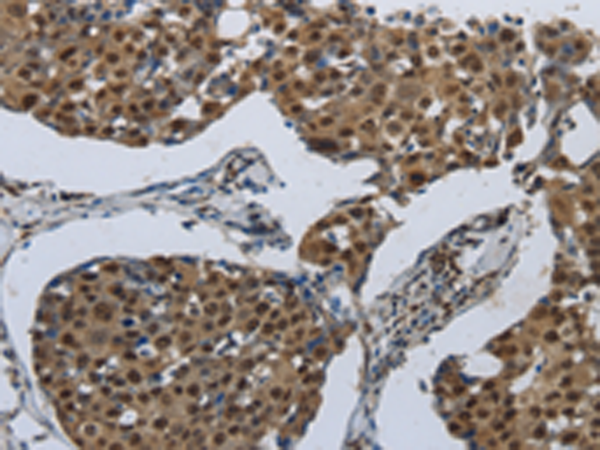

分类: 科研抗体货号: P04438别名: ROS; MCF3; c-ros-1应用: IHC反应种属: Human